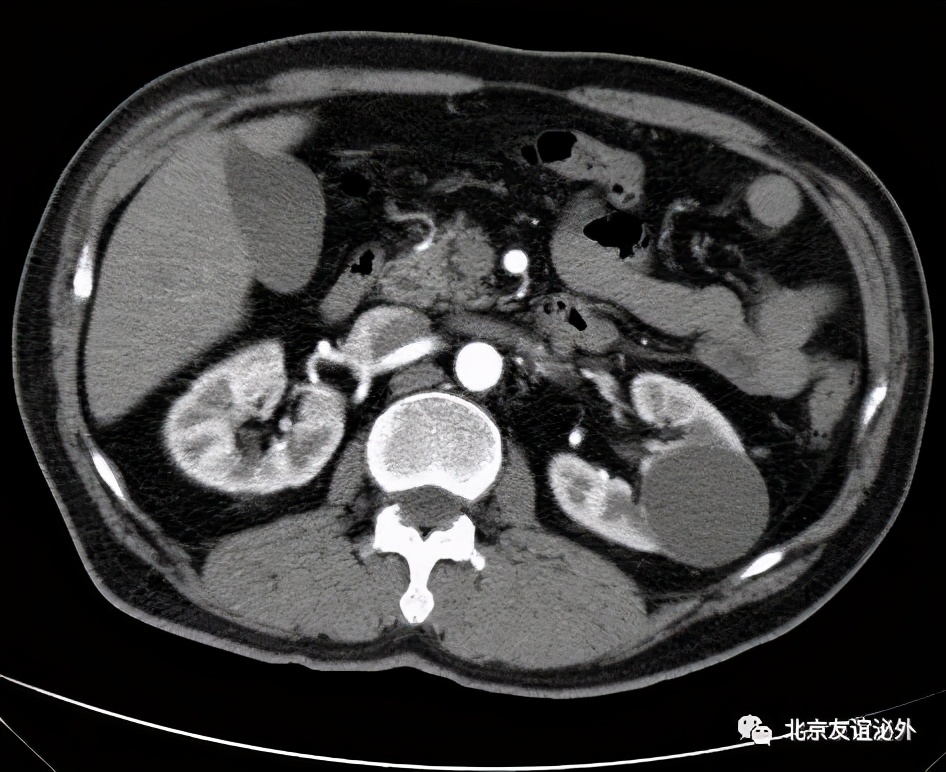

图1. Bosniak I级良性囊肿,是临床上最常见的囊肿